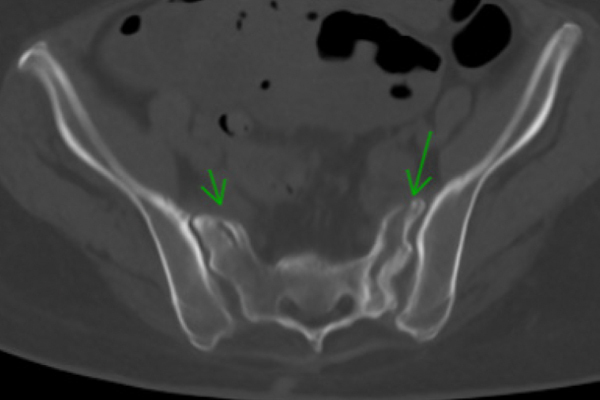

A 79-year-old female with a history of chronic lymphocytic leukemia, hyperlipidemia, hypertension, and severe osteoporosis presented with a worsening of right-sided sacral and pubic rami fractures initially sustained three months prior (Fig. 1).

Cunningham 1b